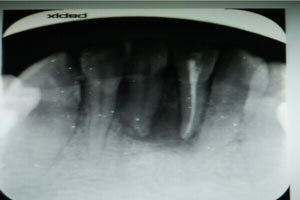

圖2.術(shù)前的根尖片影像、31根管治療已做,欠填少許。31、41根尖有橢圓形陰影,未見(jiàn)明顯骨白線。